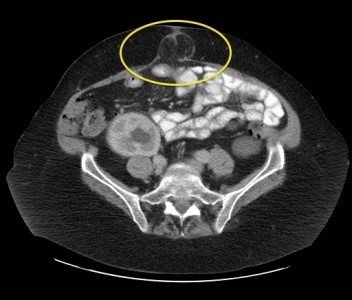

Xarici yırtıqların diaqnozu əksər hallarda klinik olaraq qoyulur, görüntüləmə üsulları erkən mərhələ yırtıqlarda, differensiasiyada, yanaşı xəstəlikləri və yırtığın ağırlaşmalarını müəyyənləşdirmək üçün tətbiq edilir. USM bütün xəstələrdə aparılır, KT isə əməliyyatdansonrakı yırtıqlarda yırtığın ölçülərini və möhtəviyyatını müəyyənləşdirmək və daxili yırtıqları təyin etmək üçün vacibdir. MRT idmançı yırtıqlarını digər xəstəliklərdən (periostit, nevralgiya və s) differensiasiyada ilk seçimdir. Yırtığa böyük şübhə olduqda lakin klinik və görüntüləmə üsulları ilə təsdiq etmək çətinliyi olanlarda laparoskopiya aparıla bilər.

• USM-də yırtıq kisəsi və Valsalva testində orqanın kisəyə yerdəyişməsi.

• KT və ya MRT-də qarın divarında defekt, yırtıq kisəsi və yırtıq möhtəviyyatının (bağırsaq, piylik, və digər) görünməsi